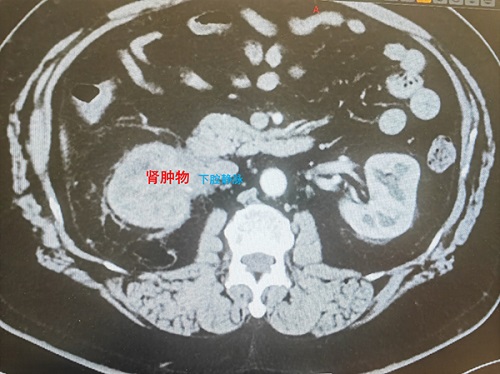

患者为53岁男性,因体检发现右肾肿物就诊。完善进一步检查,肿瘤的影像学特点极不典型,肿物侵及肾实质,右肾动、静脉显示不清,同时病灶与十二指肠及下腔静脉黏连紧密,极有可能侵及下腔静脉,为手术治疗带来巨大难度。下腔静脉作为人体最大的静脉血管,承担着下肢及腹腔脏器的血液回流功能,术中需在完整切除肿瘤的同时重建血管,对手术团队的技术水平、术中护理及麻醉的密切配合及围术期管理均提出了极高要求。

患者右肾肿物影像